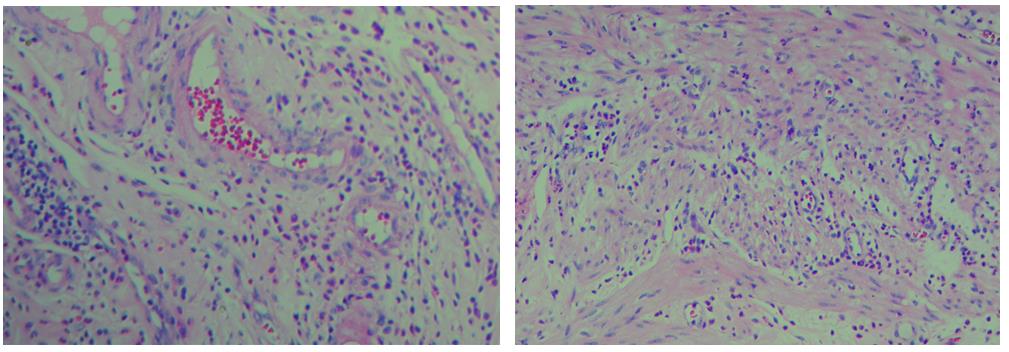

3、色彩鮮艷,核漿紅藍(lán)對比鮮明,染色效果持久穩(wěn)定,胞核結(jié)構(gòu)清晰

細(xì)胞中的細(xì)胞核由帶負(fù)電荷的酸性物質(zhì)組成,與帶正電荷的堿性染料蘇木素的氧化物三氧化蘇木紅有較強(qiáng)的親和力;而細(xì)胞漿則相反,因含有帶正電荷的堿性物質(zhì)而與帶負(fù)電的酸性染料曙紅Y的親和力較強(qiáng);細(xì)胞或組織切片經(jīng)HE染色后,細(xì)胞核被染成藍(lán)紫色,細(xì)胞漿、紅細(xì)胞、肌纖維、膠原纖維、結(jié)締組織、嗜伊紅顆粒等被染成不同程度的紅色、粉紅色或橙紅色,與藍(lán)色的細(xì)胞核形成鮮明的對比,因此更易于觀察細(xì)胞或組織中正常成份和病變成份的一般形態(tài)結(jié)構(gòu)。

【實(shí)際染色效果】